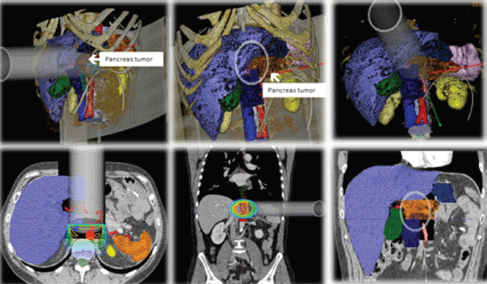

RADIANCE is the only tool designed and patented for IORT planning with US Food and Drug Administration approval and the European Community mark. Using a graphics engine, the system is capable of generating a three-dimensional image of the patient from a CT or MRI before surgery. Through segmentation on the axial, coronal, and sagittal planes, the user can generate a volumetric 3D image of organs at risk and the tumour bed. The system then determines the surgical field in real time and optimises the parameters of the applicator (cone diameter, bevel, energy, and dose). Finally, the platform allows optimisation of treatment parameters, by calculating a dose–volume histogram 4.7 (Figures 2–4).

Figure 4: IORT simulation unresectable pancreatic adenocarcinoma with RADIANCE.